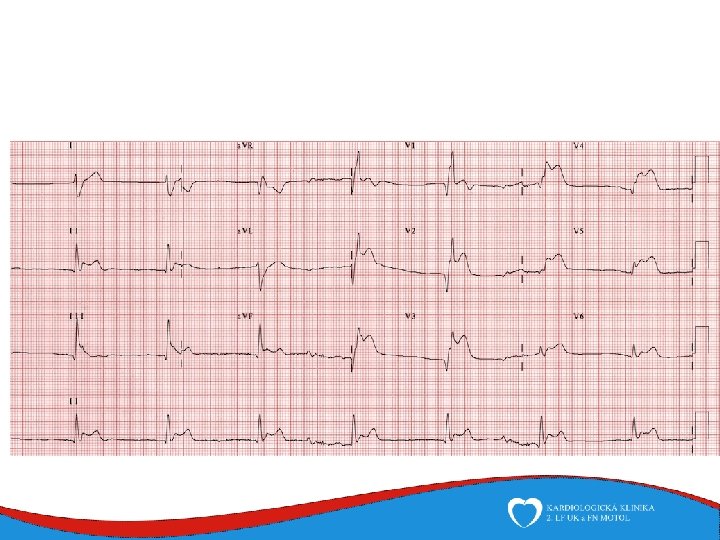

Case report Woman, 75 years Comes to ED for new-onset chest pain and weakness History: hyperthyreosis Drugs: Thyrozol Family history: no cardiovascular diseases Physical: BP 105/70, HR 92/min, RR 20 breaths/min, sat O 2 94%

ECHO – anterior wall akinesis, LV EF 35%, mild mitral regurgitation, no dilation of right-sided chambers, no pericardial effusion

Tako-tsubo